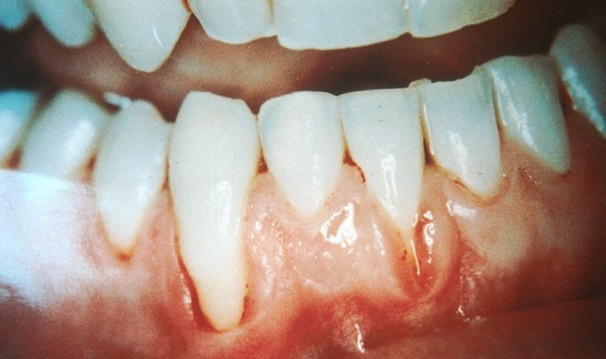

Receding Gums, Symptoms, Causes and Treatment

Gum recession is when the margin of the gum tissue surrounding the teeth wears away, or pulls back, exposing more of the tooth, or the tooth's root. When gums recede, gaps can form between the gum and tooth, allowing disease-causing bacteria to build up. If left untreated, the surrounding tissue and bone structures of the teeth can be damaged.

Receding gums is a widespread dental condition. Most people aren’t aware that they have receding gums since it occurs gradually.

Long Teeth.- One symptom is the visible lengthening of the teeth. When gums recede because of periodontal disease, the teeth have the appearance of being much longer than normal.

Exposed Roots.- Exposed roots are another symptom, and can be extremely sensitive and uncomfortable. They are often a sign of periodontal disease or can be attributed to brushing overly aggressively with a toothbrush with hard bristles.

Loose teeth.- When suffering from receding gums, you may notice loose teeth, attributed to the bacteria and periodontal disease under the gums around the teeth. As receding gums worsen, the gum pockets deepen due to loss of attachment structure.